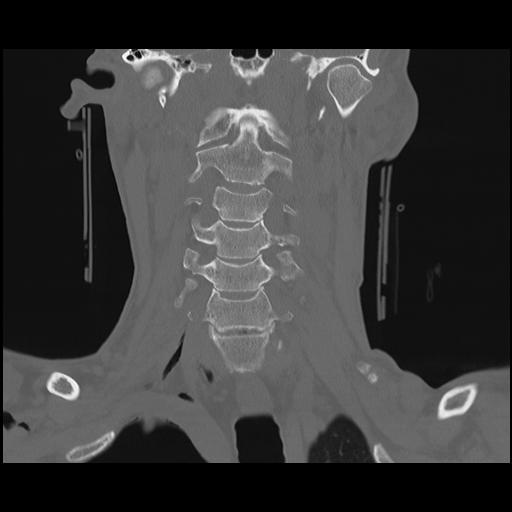

16 HUESO,,Coronal,2.000,HUESO,Coronal,